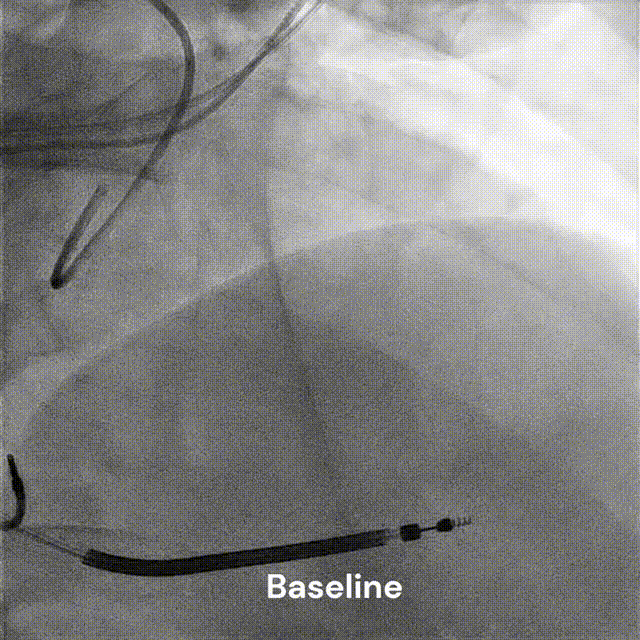

图4冠状动脉造影联合痉挛激发试验

(A)左冠状动脉造影显示无明显狭窄。(B)小剂量乙酰胆碱激发试验显示多支冠状动脉痉挛。